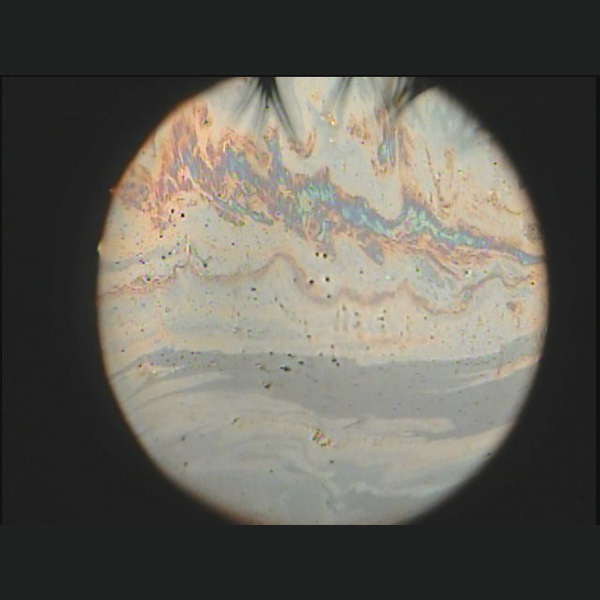

Zusätzlich zur spiegelnden Reflektionsbeobachtung kann die Aufreißzeit (NIBUT) des Tränenfilms nichtinvasiv gemessen werden.

In addition to specular reflection observation, the tear time (NIBUT) of the tear film can be measured non-invasively.